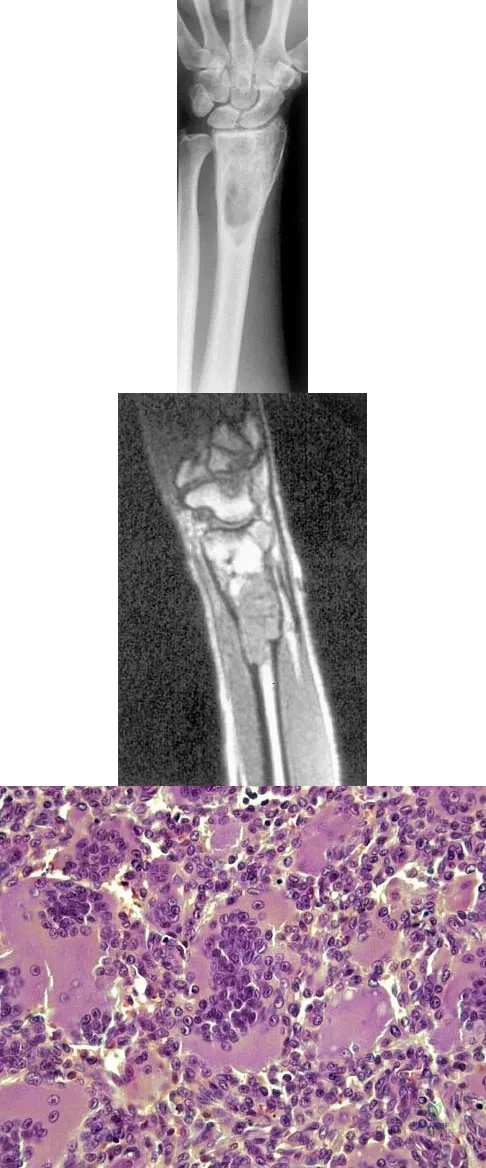

Figures 27a through 27c show the AP radiograph, MRI scan, and biopsy specimen of an otherwise healthy man who has a painful wrist. Serum chemistry studies are normal. What is the most likely diagnosis?

Explanation